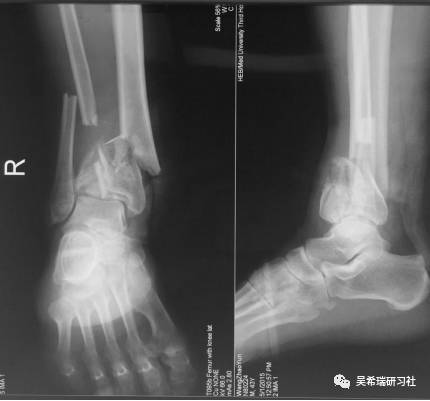

男  43岁 从2米处摔伤  开放性Pilon骨折

TIPS:关节内骨折非跨越关节固定技术一期应用骨水泥 + 开放植骨技术腓骨克氏针固定技术截骨矫形胫骨近端取骨技术